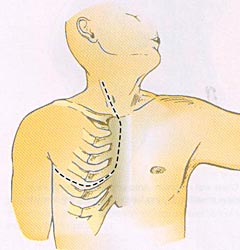

Рентгеновские снимки опухоли Панкоста